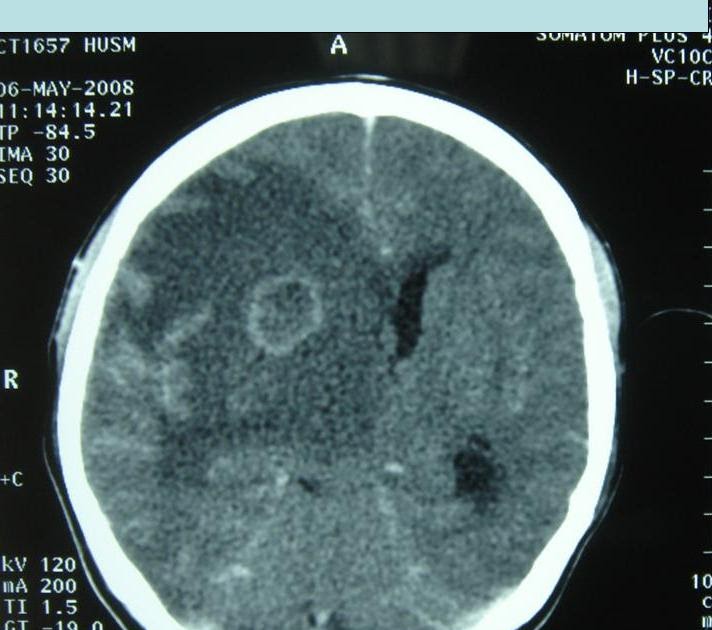

Contrast enhanced CT scan shows well defined ring enhancing lesions Ring Enhancement Abscess increased perfusion favors neoplasm (metastases or primary cerebral malignancy) central fluid content. typical imaging of toxoplasmosis, and other bacterial or viral abscesses, displays signs of central. Enhancing demyelinating lesions differ in size, shape or pattern. Ring Enhancement Abscess.

Multiple ring enhancing and solid abscesses in the supratentorial Ring Enhancement Abscess typical imaging of toxoplasmosis, and other bacterial or viral abscesses, displays signs of central. increased perfusion favors neoplasm (metastases or primary cerebral malignancy) central fluid content. Enhancing demyelinating lesions differ in size, shape or pattern. Ring Enhancement Abscess.